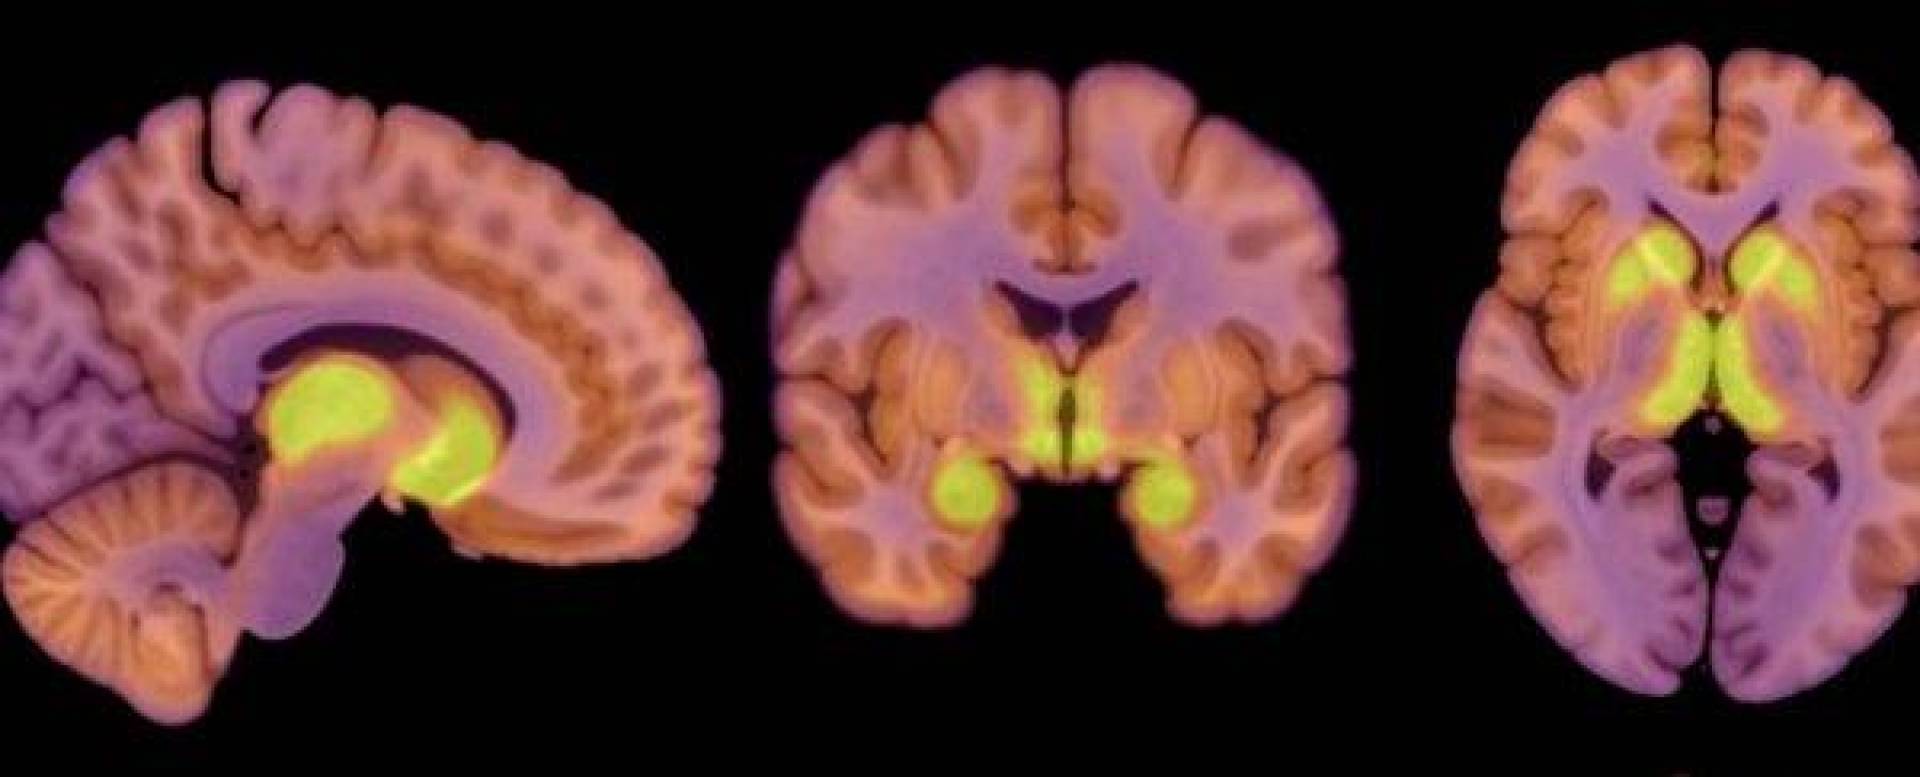

تحليل نشاط الدماغ باستخدام التصوير المقطعي بالإصدار البوزيتروني (PET)

اعتمد الباحثون على التصوير المقطعي بالإصدار البوزيتروني (PET) لقياس توفر مستقبلات MOR في الدماغ، كما استخدموا التقنية نفسها لقياس استهلاك الجلوكوز في الدماغ.